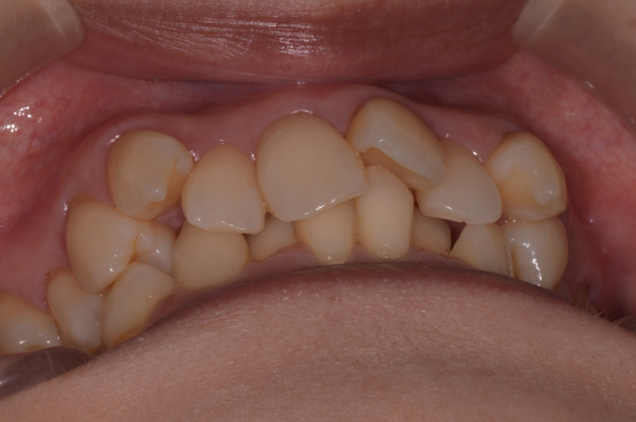

症例2

| 項目 | 詳細 |

|---|---|

| 患者様データ | 30代 女性 |

| 来院時の主訴 | 「右上の、内側に生えている歯が邪魔。」 |

| 矯正法 | 上の歯2本、下の歯2本、親知らず3本を抜歯しての矯正 |

| 通院期間 | 3年6ヶ月 |

| 治療費 | 総額:1,230,000円(税抜) 【内訳】 精密検査50,000円、メタルワイヤー矯正800,000円、月に1度の調整料5,000円、後戻り防止のリテーナー35,000円×2 |

| リスクと副作用 |

①歯を動かす事による痛みがあります。また、装置に慣れるまでは、口内炎ができやすいです。 ②歯肉が退縮するリスクがあります。装置が全ての歯に付くので、ハミガキが難しくなります。 ③長期的なメインテナンスが必要 |

| ここがこだわりのポイント!☝ | こちらの患者様は上の歯が1本内側に生えていましたが、奥歯の噛み合わせの方が問題でした。ハサミ状咬合といい、奥歯が極端に外側に向いており、下の歯と噛み合っていない状態でした。ハサミ状咬合は長期的にみると、前歯に大きな負担がかかったり、磨きにくい事による虫歯や歯周病になりやすいなどのリスクがあります。治療期間はかかりましたが、見た目の良さだけでなく、機能的にも改善しました。 |